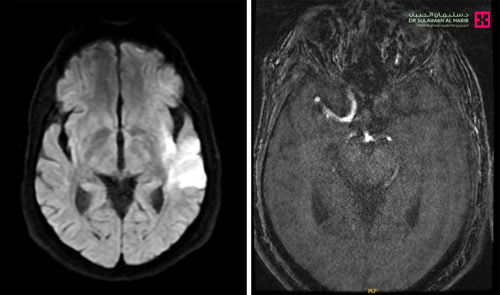

شَهِد مستشفى الدكتور سليمان الحبيب بالصحافة، إنقاذ حياة رجل في العقد السادس من العمر، مصاب بانسداد في الشريان السباتي، وعانى من أعراض حادة، وتمكن فريق طبي متخصص بالمستشفى من إزالة الخثرة، عبر تقنية القسطرة التداخلية دون فتح جراحي، وإعادة حركة الدم إلى وضعها الطبيعي. ذكرت ذلك د. فرح العيسى استشارية المخ والأعصاب والأشعة التداخلية، رئيسة الفريق الطبي المعالج. وقالت د. العيسى إن المريض أسعف إلى المستشفى بعدما أصيب بشكل مفاجئ بشلل نصفي تام، وتدن في الإدراك والفهم، وعدم القدرة على التواصل مع الآخرين وصعوبات في النطق، وعلى الفور أجريت له فحوصات دقيقة للتأكد مما إذا كان المراجع مصاباً بالسكتة الدماغية أو مشكلات أخرى.

وأضافت أن النتائج أظهرت وجود انسداد بالشريان، وأكد الفريق الطبي على أهمية التدخل العاجل عبر تقنية القسطرة التداخلية، لمحاصرة التبعات ومنع تطورها إلى السكتة الدماغية، حيث تمت إزالة انسداد الشريان السباتي باستخدام قسطرة دقيقة مثبت بطرفها أنبوب صغير، استُخدم لفتح الشريان المنغلق بقاع الجمجمة وتوسيعه، ومن ثم زراعة دعامة دائمة في المنطقة المتضررة للحيلولة دون حدوث الانسداد مرة أخرى، مؤكدة أن التدخل العلاجي تكلل بالنجاح التام، حيث نُقِل المريض بعلامات حيوية مستقرة إلى وحدة العناية المركزة وبقى قيد المراقبة الطبية لمدة «24» ساعة، وتحسنت حالته بعد العملية مباشرة، حيث استعاد القدرة على الحركة، والمشي بدون مساعدة، كما تحسنت قدرته على الكلام والتواصل مع الآخرين، بالإضافة إلى أن مستوى الفهم والإدراك ارتفع إلى «70 %»، وفي اليوم التالي للتدخل الطبي أعيد فحصه بالأشعة فأظهرت النتائج عودة حركة الدم عبر الشريان إلى طبيعتها، كما تبين أن السبب الأساسي للإصابة تعود إلى عدم انتظام ضربات القلب. وأوضحت د. العيسى أن المريض غادر إلى منزله بحالة صحية جيدة، لكنه سيخضع لبرنامج علاج تأهيلي، مشيرة إلى أن نجاح العملية جنبه الكثير من التبعات الصحية الوخيمة.